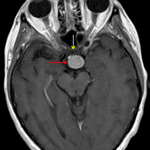

MRI

- T1/T2/FLAIR isointense, diffusely enhancing suprasellar mass measuring 1.8 x 1.4 x 1.7 cm

- Predominantly peripheral corresponding susceptibility artifact corresponding with calcification seen on CT

- The mass is centered on the pituitary stalk and is seen separate from the pituitary gland

- The mass contacts the optic tracts and posterior aspect of the optic chiasm

Papillary craniopharyngioma